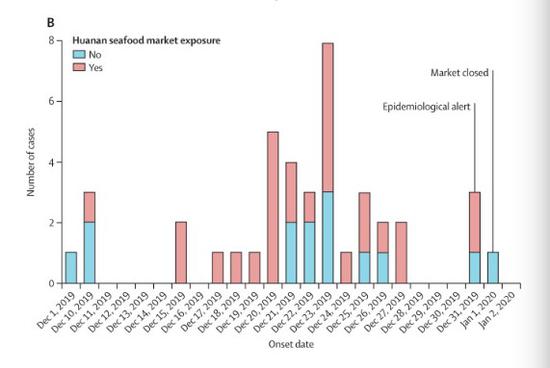

新京报快讯(采访人员 许雯 陈沁涵)国际医学期刊柳叶刀1月24日在线发表的一项研究显示,首例新型冠状病毒肺炎确诊患者于去年12月1日发病,且无华南海鲜市场暴露史。

研究分析了2019年12月16日至2020年1月2日期间在武汉市入院的首批41例确诊感染新型冠状病毒的病例。结果显示,首批41例确诊病例中,27例去过华南海鲜市场,14例没有华南海鲜市场暴露史。

最初发病的4例确诊患者中,有3例无华南海鲜市场暴露史。其中,首例确诊患者的发病日期为2019年12月1日,他的家人均未出现发烧或任何呼吸道症状。该患者无华南海鲜市场暴露史,和之后的病例之间也没有发现流行病学联系。

这比官方通报的最早发病日期提前了7天。在武汉卫健委1月5日发布的第三份官方通报中,提及患者最早发病时间为2019年12月12日。1月11日官方通报中将最早发病日期更新为2019年12月8日。